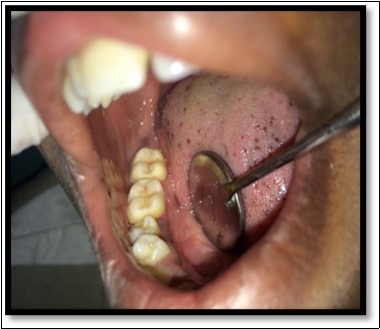

Figure 2.Excised lesion

Excised lesion

During the next visit local anesthesia was given. The lesion was excised with the help of soft tissue laser and sent for histological examination. (Figure 2) Histological report confirmed the lesion is Peripheral cemento-ossifying Fibroma. Histological analysis showed lesional tissue comprising of both trabecular bone and woven bone. Periphery of the lesion showed numerous globular and irregular cementum like calcification. In most areas these calcification coalesced with each other forming bigger calcification. The supporting connective tissue stroma was loose fibrillar with less cellularity. Detached overlying parakeratinized epithelium was observed in one area. (Figure 3) Post operative evaluation revealed normal healing after one month. (Figure 4)